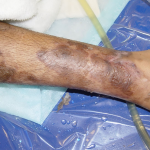

Pemphigis Vulgaris =الفقاع الشائع